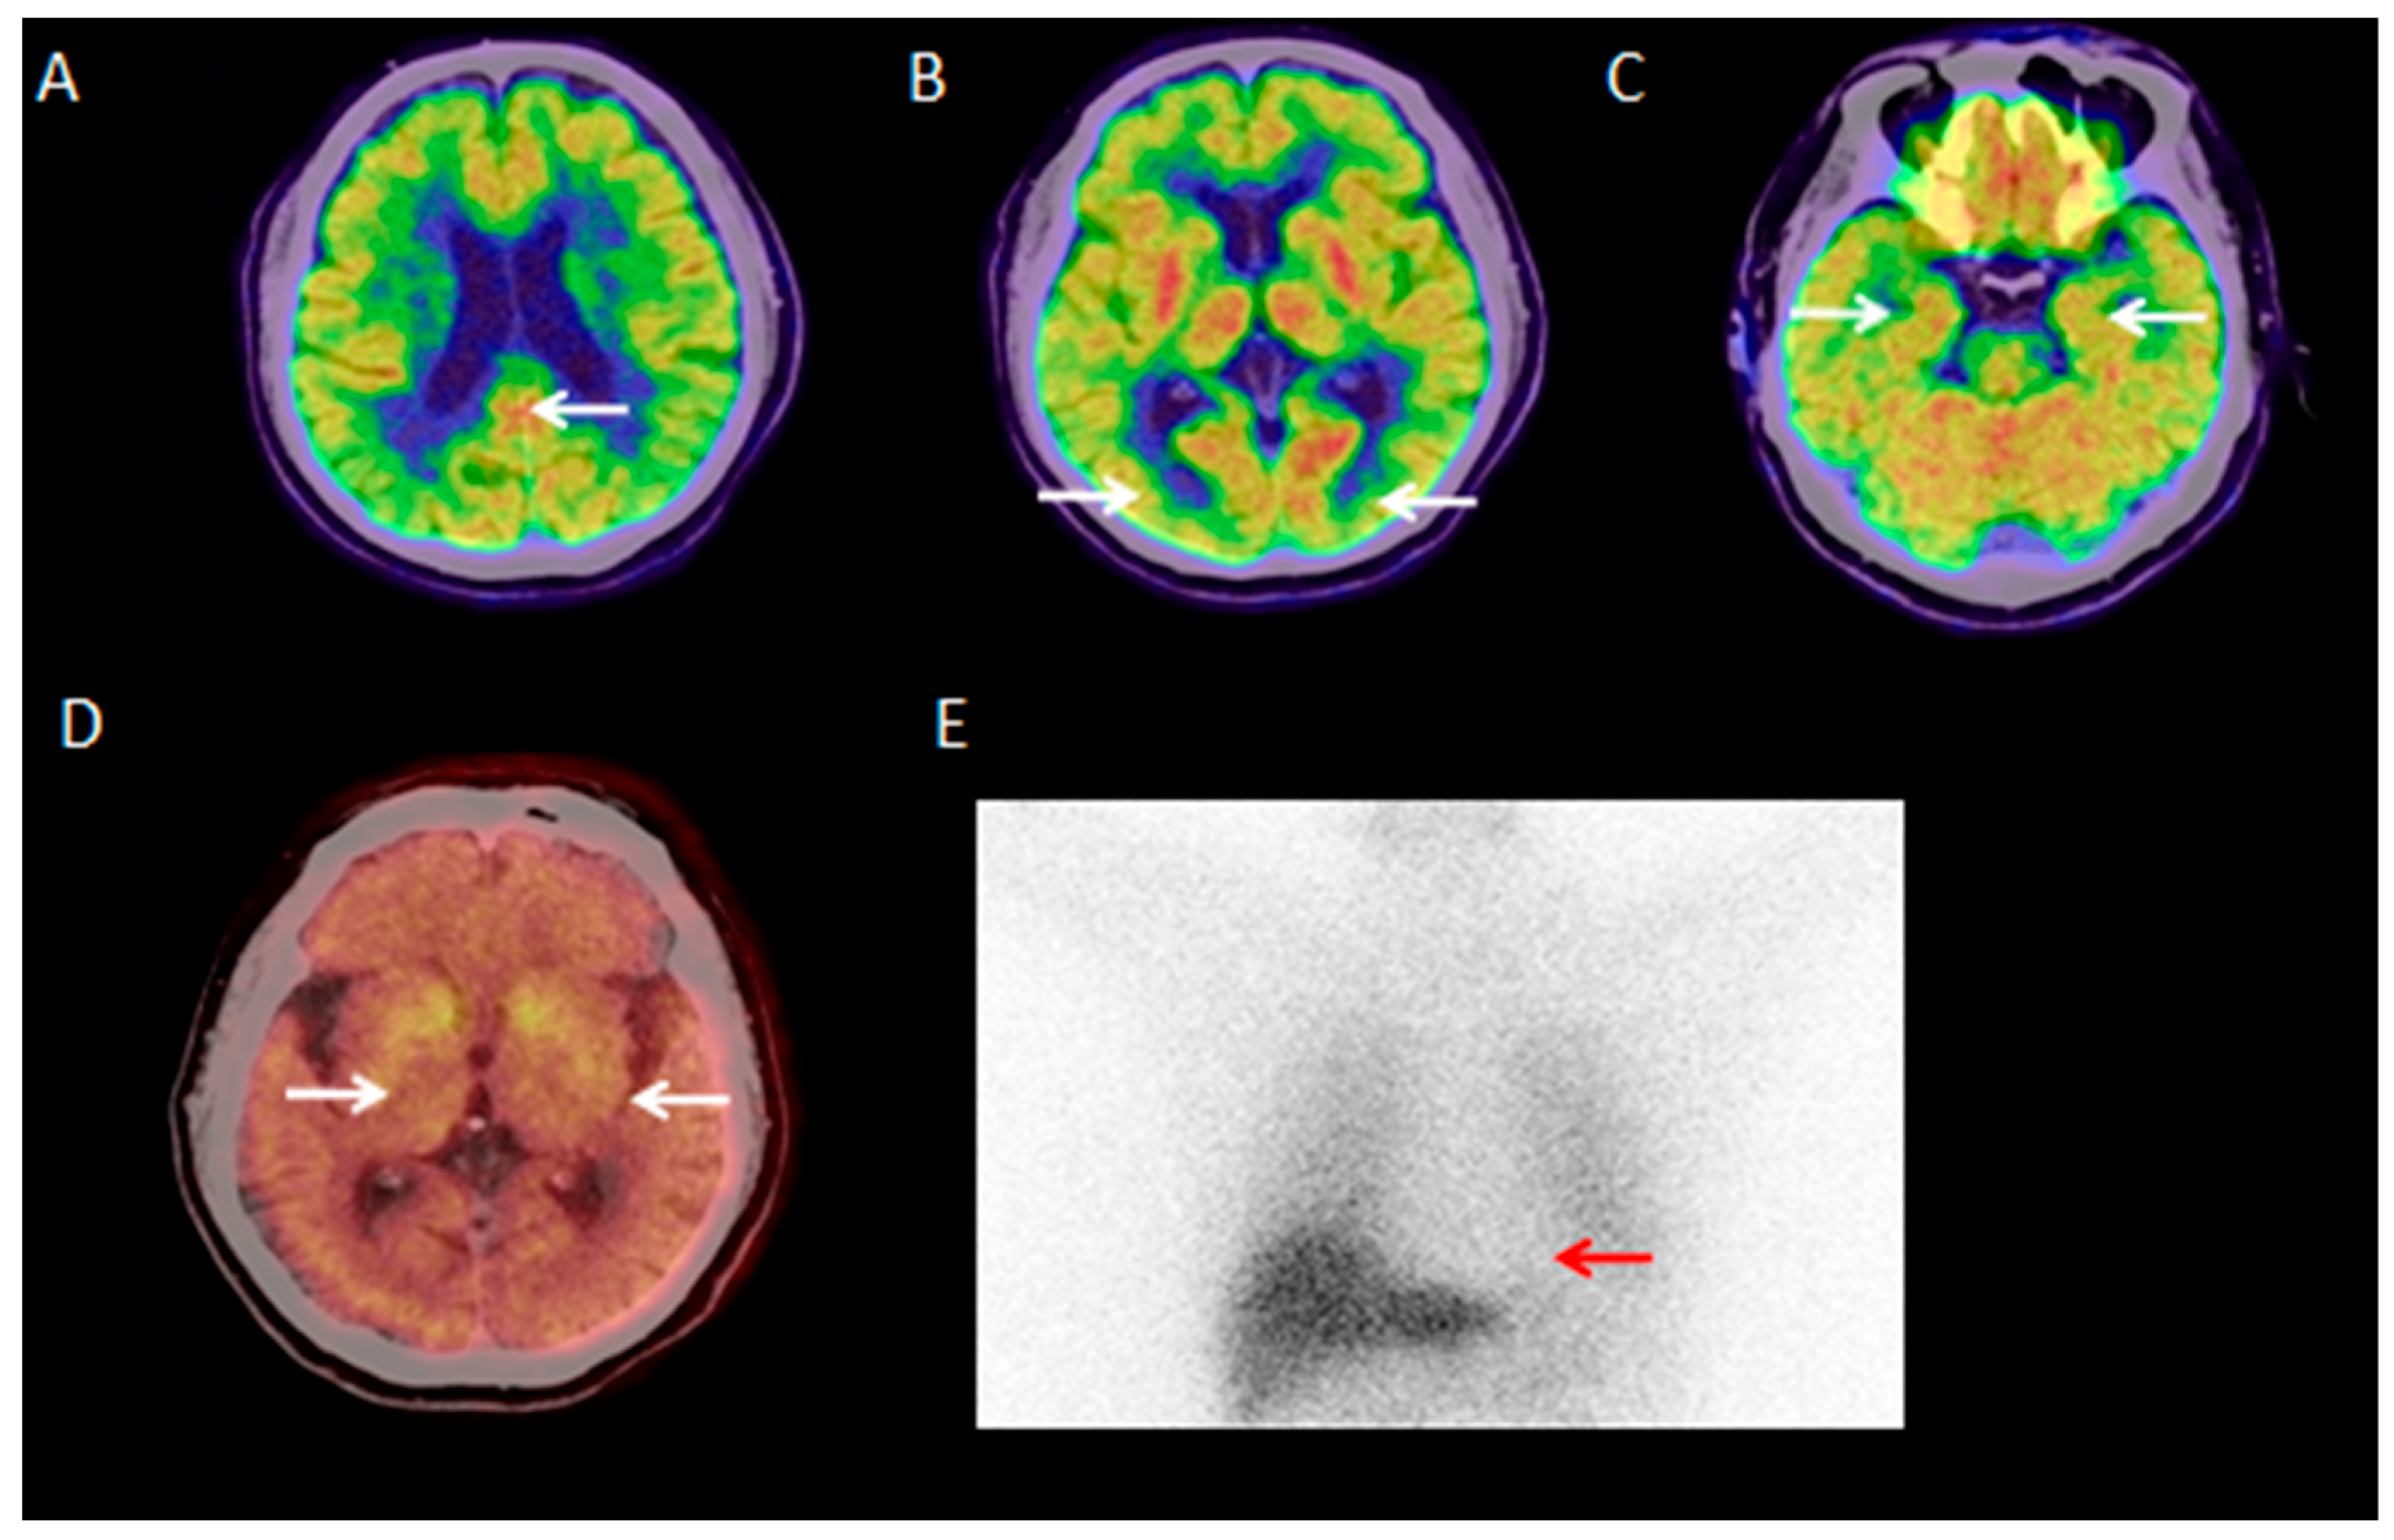

3.2.1. Visual Analysis of 18F-FDG PET/CT

3.2.4. Visual Analysis of 18F-AV45 PET/CT

3.2.6. Visual Analysis of 18F-FP-CIT PET/CT

3.2.7. Visual Analysis of 131I-MIBG SPECT